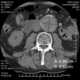

Aortic thrombosis

An aortic aneurysm is an enlargement (dilatation) of the aorta to greater than 1.5 times normal size. They usually cause no symptoms except when ruptured. [Source: Wikipedia ]